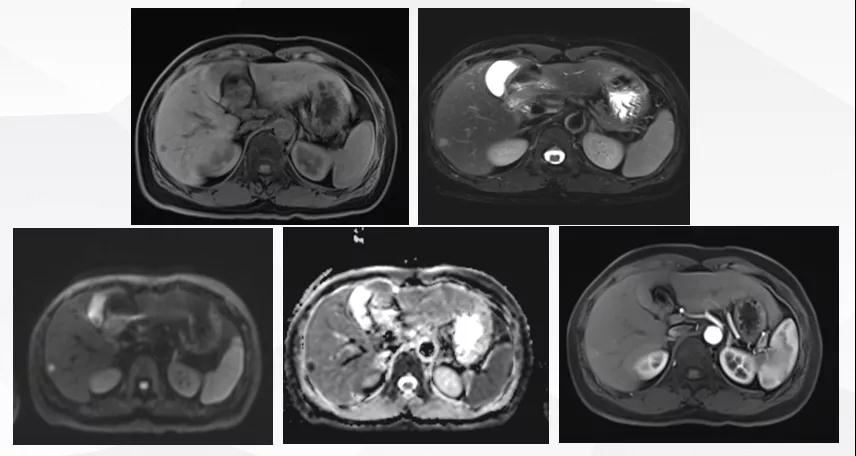

给予T-DM1治疗。治疗6个月后复查MR显示脑、肝、骨转移瘤均较前明显缩小,达到部分缓解(PR)(图2)。目前PFS已达10+个月。

患者为ⅢA期(cT3N1M0)、三阳性乳腺癌,经AC-TH新辅助治疗达到降期(ypT2N0M0)。患者内分泌+抗HER2辅助治疗结束6个月时出现转移进展(脑、肝、骨),给予THP一线治疗,因无法耐受毒副作用而改为T-DM1,治疗6个月达到肝、脑、骨转移PR,患者目前中位PFS已超过10个月,T-DM1治疗过程中仅出现轻度CIT,且可自行恢复。